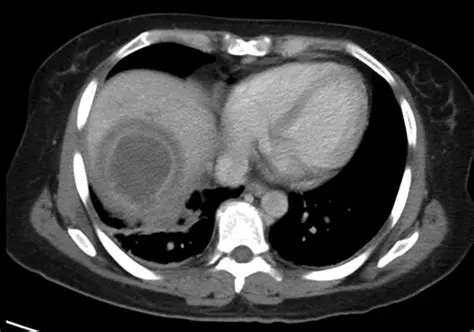

Ameba Liver Abscess Diagnosis